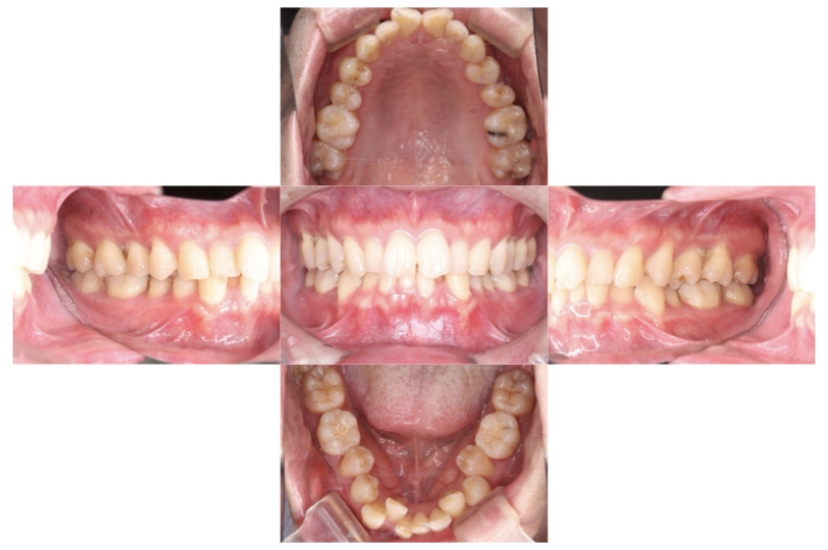

BEFORE

AFTER

症例2

上下顎前突、叢生

抜歯

ブラケット矯正

上下顎前突、叢生(上下出っ歯、上下の前歯のガタガタ)のケースです。

装置はラビアル(上下表側)で、上下顎の小臼歯を4本抜歯を行っています。抜歯したスペースを使って、上下の前歯の後方移動と叢生(ガタガタ)の改善を行っています。

主訴 前歯のガタガタと口元がでているのが気になる。

年齢・性別 30歳 女性

お住まいの地域 東京都大田区

治療方針 抜歯スペースを利用して上前歯の叢生(ガタガタ)と口元突出の改善

抜歯部位 上下顎左右第一小臼歯

使用装置 ラビアル(上下表側)、顎間ゴム

治療期間 1年11か月

治療回数 13回

リテーナー クリアリテーナー